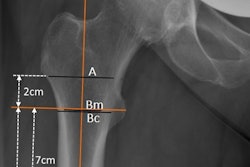

The images were used first to train and validate a DenseNet-121 convolutional neural network (CNN), which was selected based on its comparatively fewer parameters and faster training time, the authors noted. The presence of a hip fracture was defined as any fracture involving the proximal femora, with ground-truth labels (hip fracture present or absent) determined by two expert radiologists.

A graphical abstract. Courtesy of iScience.Of the 18,803 pelvic x-rays performed in the ED, 3,761 (20%) were randomly selected to form a holdout test set for subsequent evaluation of the model. This was done "to better approximate the potential real-world use scenario, " where patients with suspected hip fractures present almost exclusively to EDs, the authors wrote.

The holdout set contained 463 images (12.3%) that were positive for hip fracture. Orthopedic implants in either the proximal femur or the bony pelvis were also present in a significant proportion of the images, the researchers noted.